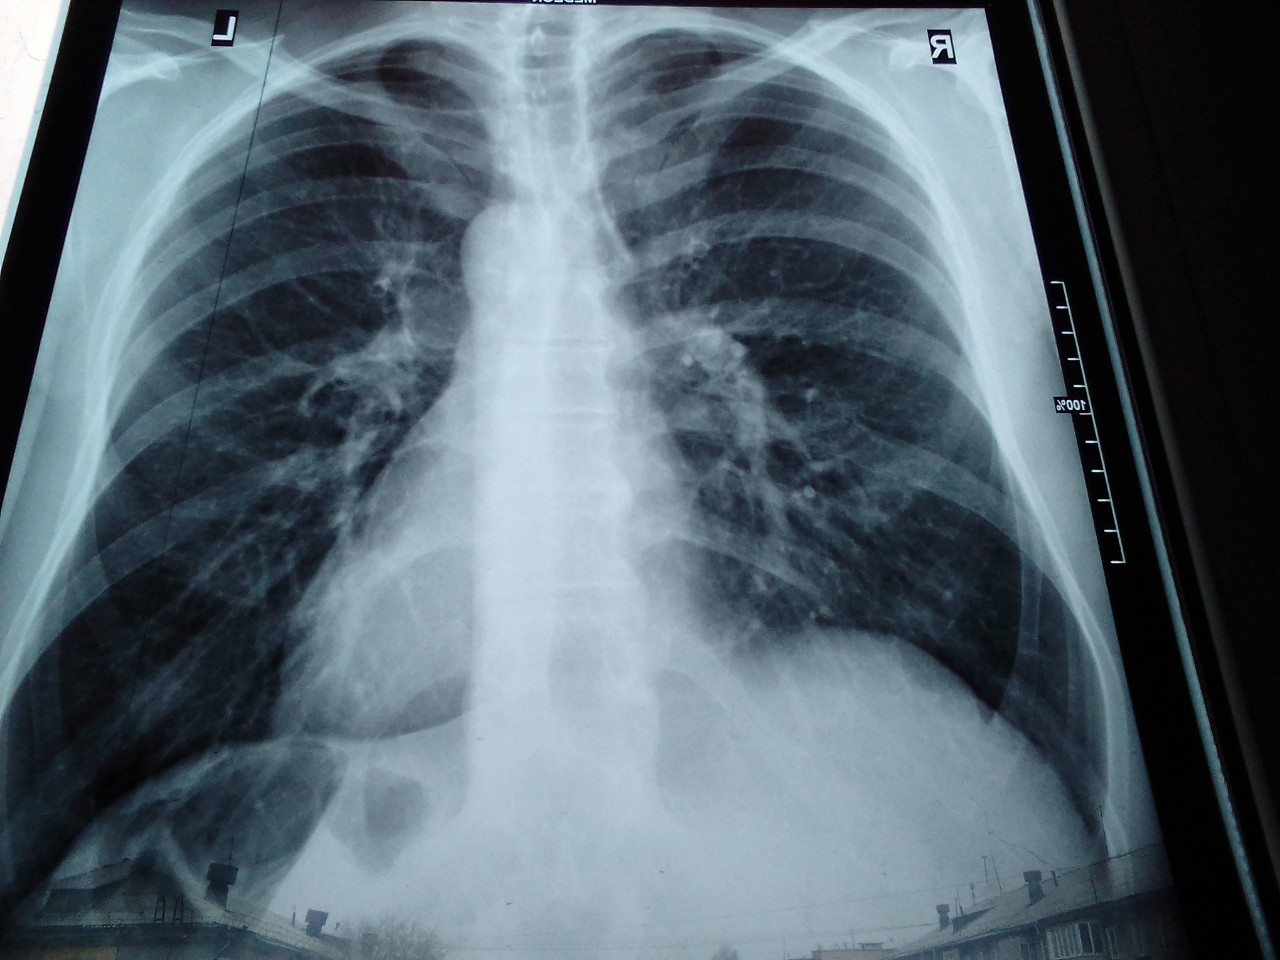

Нормальная рентгенограмма легких: что нужно знать

Раздел: Мудрость в объективе